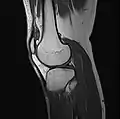

MRI

Both anterior cruciate ligament (ACL) and posterior cruciate ligaments (PCL) are hypointense on both T1 and T2 weighted images of MRI. However, some high signal striations are often seen at the distal part of the ACL, making ACL higher intensity than PCL on MRI scans.[17]

- Knee MRI osteoarthritis (sagittal TSE FS)

- Knee MRI osteoarthritis (sagittal T1 TSE)

- Knee MRI osteoarthritis (coronal T2 TSE FS)

- Knee MRI osteoarthritis (traverse PD TSE FS)